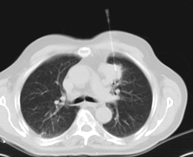

- Chest CT

Diagnostic test that provides high definition anatomical images of the chest (lungs, heart, mediastinum, great vessels, rib cage, etc.) using CT (Computed Tomography) equipment. These images are then examined on a workstation that allows bidimensional reconstructions in different planes of space and also 3D reconstructions (volumetric). Some studies require the use of an iodinated contrast agent to improve image definition.

- High resolution Chest CT

Diagnostic test to examine the lung using CT (Computed Tomography) equipment to obtain two- and three-dimensional images, that allow a highly specific anatomical examination of the lung, being able to assess very small anatomical structures. This technique is very important among patients with suspected lung disease.